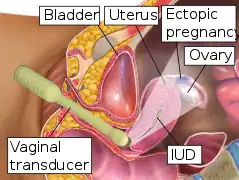

Transvaginal ultrasonography

An ultrasound showing a gestational sac with fetal heart in the fallopian tube has a very high specificity of ectopic pregnancy. It involves a long, thin transducer, covered with the conducting gel and a plastic/latex sheath and inserted into the vagina.[32] Transvaginal ultrasonography has a sensitivity of at least 90% for ectopic pregnancy.[5] The diagnostic ultrasonographic finding in ectopic pregnancy is an adnexal mass that moves separately from the ovary. In around 60% of cases, it is an inhomogeneous or a noncystic adnexal mass sometimes known as the "blob sign". It is generally spherical, but a more tubular appearance may be seen in case of hematosalpinx. This sign has been estimated to have a sensitivity of 84% and specificity of 99% in diagnosing ectopic pregnancy.[5] In the study estimating these values, the blob sign had a positive predictive value of 96% and a negative predictive value of 95%.[5] The visualization of an empty extrauterine gestational sac is sometimes known as the "bagel sign", and is present in around 20% of cases.[5] In another 20% of cases, there is visualization of a gestational sac containing a yolk sac or an embryo.[5] Ectopic pregnancies where there is visualization of cardiac activity are sometimes termed "viable ectopic".[5]

Transvaginal ultrasonography of an ectopic pregnancy, showing the field of view in the following image

Transvaginal ultrasonography of an ectopic pregnancy, showing the field of view in the following image A "blob sign", which consists of the ectopic pregnancy. The ovary is distinguished from it by having follicles, whereof one is visible in the field. This patient had an intrauterine device (IUD) with progestogen, whose cross-section is visible in the field, leaving an ultrasound shadow distally to it.